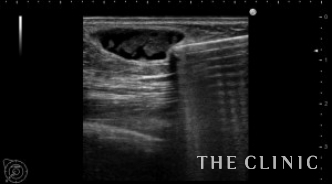

充実性のしこりは、ベイザーリポで崩して吸引しました。

オイルシストは穿刺吸引しました。

ベイザーで吸引した脂肪と穿刺吸引したオイルシストです。